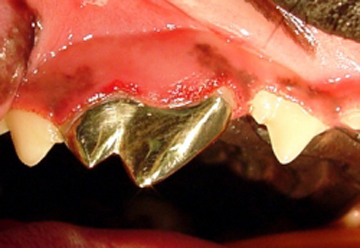

En el caso de la gingivitis, se clasifica según el tejido presente como “Gingivitis simple” en la cual la encía libre y papilar se encuentra hiperémica y sangrante; “Gingivitis hiperplásica” cuando la encía se encuentra con un aumento muy considerable en su tamaño y presenta un tejido inflamatorio hiperémico, sangrante e hiperplásico; y “Gingivitis hiperplásica fibrosa” cuando la encía está muy aumentada de tamaño y con una gran cantidad de tejido fibroso que se caracteriza por no ser hiperémico ni sangrante, sino que es de color rosa muy claro e inclusive hasta blanco y muy duro. Una de las características de las gingivitis hiperplásica y la gingivitis hiperplásica fibrosa es la presencia de bolsas periodontales falsas, ya que al medir la profundidad del surco este aparece aumentado, pero es debido al aumento del tamaño de la encía libre y papilar y no a la perdida de estructura ósea alveolar.